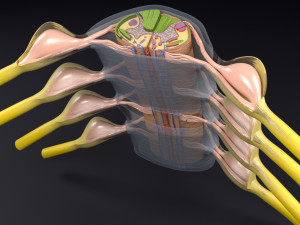

spinal fixation system - titanium bracket. human spine, spinal cord, sacrum and fixation system medically accurate high quality 3d model.

hi-poly 3d model of human spine with internal structure.

더 보기hi-poly 3d model of human spine with internal structure.